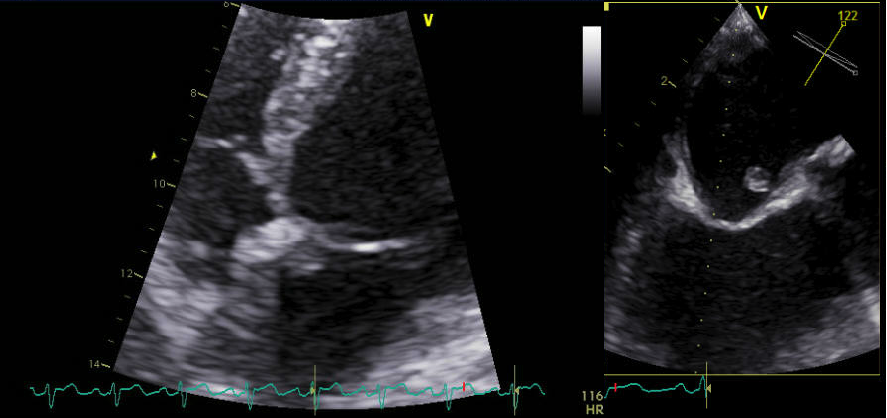

Patient was assessed with Transthoracic echocardiography (TTE) which showed mild left ventricular dysfunction (with ejection fraction of 40%) and a small mass attached to the lower interatrial septum (Figure 8). The findings were confirmed in transesophygeal echocardiography (TEE) study that described a pedunculated mass seen at the lower interatrial septum measured 0.8x0.6x0.5 cm (Figure 9 and 10) close to mitral aortic continuity. This was consistent with left atrial myxoma.

Figure 8: 2-D TTE in apical 4-chamber view and 2-D TEE showing small pedunculated myxomal mass measuring 0.8x0.6x0.5 cm attached to the lower interatrial septum on left atrial side.

Figure 9: 3-Dimantional TEE showing the myxomatous remnant attached to the interatrial septum near the base atrial mitral leaflet.